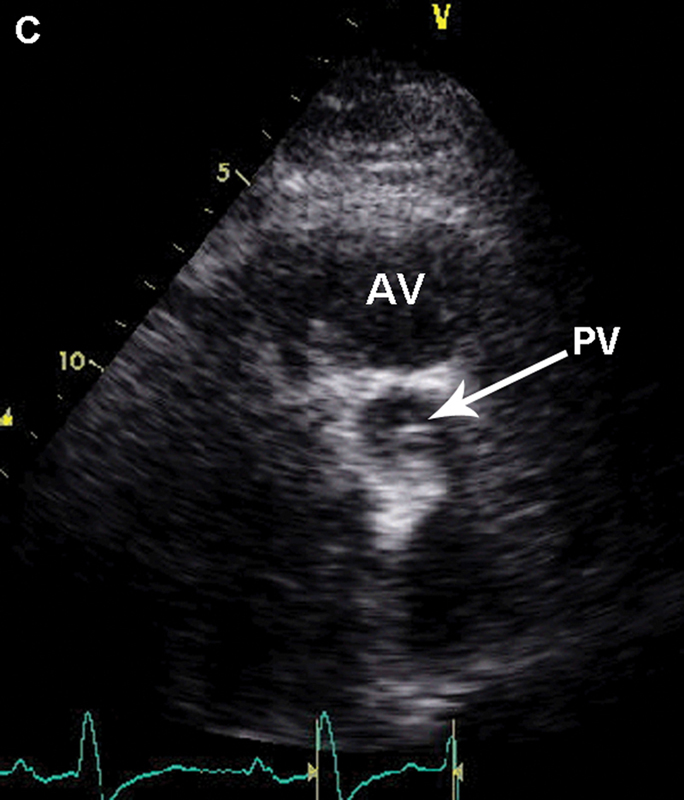

فحوصات تشخيصية لبعض امراض القلب والشرايين التاجية